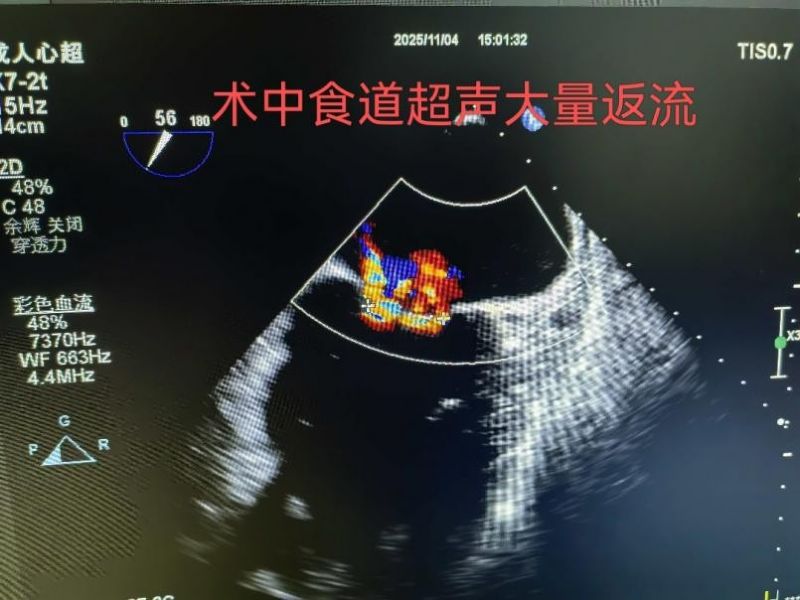

患者文先生5年前曾患急性心肌梗死,此后反復出現胸悶、氣短癥狀,活動能力逐年下降。入院檢查顯示,其心臟射血分數(EF)僅為39%(正常范圍50%-70%),二尖瓣返流面積達13.4cm2,左心房擴大至74mm,傳統外科手術風險較高。經心血管內科、心臟外科等多學科會診后,醫療團隊推薦采用TEER技術進行治療。主管醫生王銀濤就“經導管二尖瓣緣對緣修復術(TEER)”與家屬達成意向。

手術于11月4日下午進行,通過股靜脈穿刺送入夾合器,在食道超聲實時引導下,精準植入2枚瓣膜夾修復二尖瓣。整個過程歷時約2小時,術中出血量僅50ml。術后次日,患者即可下床活動,復查顯示EF提升至46%,二尖瓣返流面積縮小至3.0cm2,左心房縮小至66mm,胸悶、氣短癥狀明顯緩解。